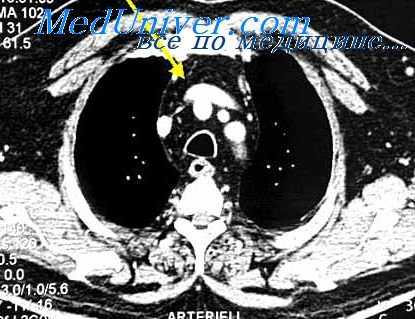

После выделения опухоли средостения пальпируют ее. При ощущении флуктуации можно предположить, что это киста средостения. Следует быть осторожным, чтобы не принять аневризму за другое образование средостения. Тератомы, лимфангиомы, лимфомы и некоторые разновидности саркомы иногда имеют смешанную структуру (содержат твердые, жидкие и замазковидные части). В некоторых опухолях пальпируются плотные участки кальцифицированной ткани (дермоидные кисты, тератомы, лимфомы). Если жидкое содержимое находится под сильным напряжением, киста может лопнуть. Нередко вылущивание опухоли затруднено из-за ее больших размеров. В таком случае киста тщательно и осторожно выделяется, а затем ее пунктируют и жидкое содержимое отсасывают. Место пункции зашивают или лигируют. Подозрение на наличие аневризмы (сходное расположение, пульсация) проверяют, производя пробную пункцию тонкой иглой. Отсутствие крови при пункции еще не исключает возможности аневризмы, которая может быть заполнена слоистым организовавшимся тромбом!

Прежде чем перейти к экстирпации опухоли, необходимо произвести осмотр и топографически сориентироваться в отношении связи опухоли с окружающими органами (большими сосудами, перикардом, легким, бронхами, средостением, нервами и спинно-мозговым каналом). Идя сверху вниз, разъединяют окружающую опухоль (кисту) медиастинальную плевру. Нередко при этом проникают в район прохождения трех основных нервных стволов (в заднем средостении — симпатическая цепочка, в средней части средостения — блуждающий нерв, а в переднем — диафрагмальный нерв). Эти нервные стволы необходимо щадить. Доброкачественные опухоли и кисты окружены капсулой, хорошо дифференцированной от окружающих тканей. Их можно легко выделить, отпрепарировать и удалить. Некоторые из злокачественных опухолей прорастают в окружающие ткани; это обстоятельство во многом определяет операбильность данного процесса. Часть перикарда, диафрагмы или легкого может быть удалена вместе с опухолью. Проникновение опухоли в крупные сосуды, сердце и грудную стенку онкологически означает инкурабильность, даже в тех случаях, когда в техническом отношении экстирпация опухоли возможна. В связи с многообразием опухолей средостения следует особо рассмотреть специальные вопросы операционной техники.